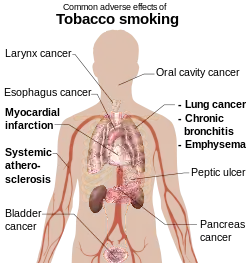

Tobacco smoking harms health because of the toxic chemicals in tobacco smoke, including carbon monoxide, cyanide, and carcinogens, which have been proven to cause heart and lung diseases and cancer. Thousands of different substances in cigarette smoke, including polycyclic aromatic hydrocarbons (such as benzopyrene), formaldehyde, cadmium, nickel, arsenic, tobacco-specific nitrosamines, and phenols contribute to the harmful effects of smoking.[105]

According to the World Health Organization, tobacco is the single greatest cause of preventable death globally.[3] WHO estimates that tobacco caused 5.4 million deaths in 2004[106] and 100 million deaths over the course of the 20th century.[3] Similarly, the United States Centers for Disease Control and Prevention describe tobacco use as "the single most important preventable risk to human health in developed countries and an important cause of premature death worldwide."[107] Due to these health consequences, it is estimated that a 10 hectare (approximately 24.7 acre) field of tobacco used for cigarettes causes 30 deaths per year – 10 from lung cancer and 20 from cigarette-induced diseases like cardiac arrest, gangrene, bladder cancer, mouth cancer, etc.[108]

The harms caused by inhaling tobacco smoke include diseases of the heart and lungs, with smoking being a major risk factor for heart attacks, strokes, chronic obstructive pulmonary disease (emphysema), and cancer (particularly cancers of the lungs, larynx, mouth, and pancreas). Cancer is caused by inhaling carcinogenic substances in tobacco smoke.

Inhaling secondhand tobacco smoke (which has been exhaled by a smoker) can cause lung cancer in nonsmoking adults. In the United States, about 3,000 adults die each year due to lung cancer from secondhand smoke exposure. Heart disease caused by secondhand smoke kills around 46,000 nonsmokers every year.[109]

In children, exposure to secondhand tobacco smoke is associated with a higher incidence and severity of respiratory illnesses, middle ear disease, and asthma attacks. Each year in the United States, secondhand smoke exposure causes 24,500 infants to be born with low birthweight, 71,900 preterm births, 202,300 episodes of asthma, and 790,000 health care visits for ear infections.[110]